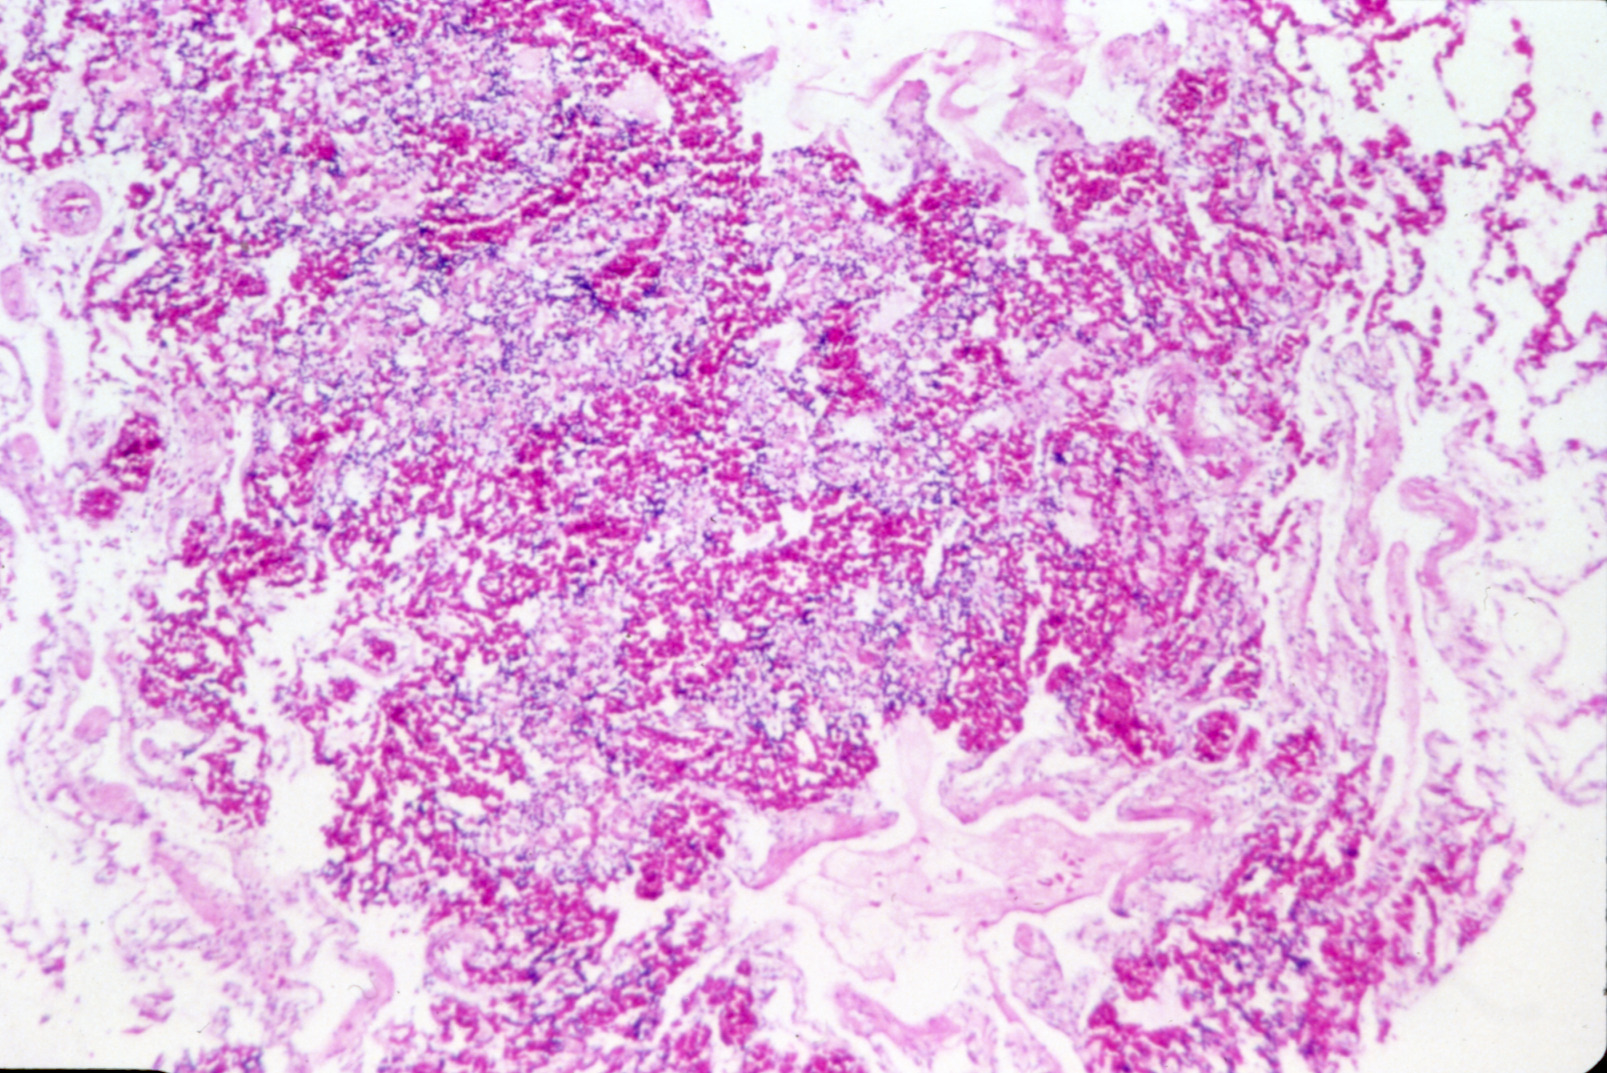

Marble spleen disease of ring-necked pheasants (slide study set no. 17) Item Info

Marble spleen disease of ring-necked pheasants (slide study set no. 17)

Poultry--Diseases Spleen--Diseases Ring-necked pheasant

Slide Study Set #17, Marble Spleen Disease of Ring-Necked Pheasants (includes 20 color slides), 1992